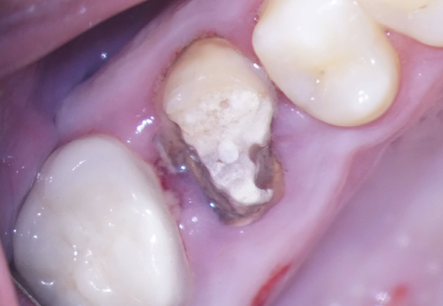

În acest caz, pacientul s-a prezentat după un abces acut în antecedente (durere puternică și spontană, cu caracter pulsatil) care a fost tratat cu antibiotice. La analiza imagisticii 3D remarcăm că există o comunicare între materialul din interiorul dintelui și spațiul dintre cele două rădăcini. Se mai evidențiază și material extrudat în acest spațiu, precum și pierdere osoasă. Deducem că este vorba de pierdere osoasă în furcație în urma cimentării unui pivot turnat. Acest pivot a fost cimentat într-un spațiu artificial creat în afara rădăcinii, această acțiune fiind un accident al tratamentului inițial (Fig. 4.12.4). Prima măsură este de a asigura izolarea cu diga dentară. Dintele prezintă o coroană artificială ce trebuie îndepărtată, diga ferește pacientul de contactul cu pulberile rezultate în urma tăierii coroanei (Fig. 4.12.5).

Pivotul de metal este voluminos și cimentat în două dintre canale și în perforație, așa că trebuie segmentat pentru a fi îndepărtat (Fig. 4.12.5, Fig. 4.12.6, Fig. 4.12.7).

După îndepărtarea unui segment din pivot, vedem cavitatea artificială care traversează grosimea dintelui, până în țesutul de susținere (Fig. 4.12.8). În țesutul de susținere se observă un material albastru, gumos. Este cel mai probabil un material din clasa silicaților, folosit pentru amprentarea spațiului din interiorul dintelui pentru confecționarea pivotului metalic (Fig. 4.12.9). Reușim să îndepărtăm o parte a acestui material și închidem perforația folosind un ciment bioceramic (MTA) (Fig.4.12.10, Fig. 4.12.11).